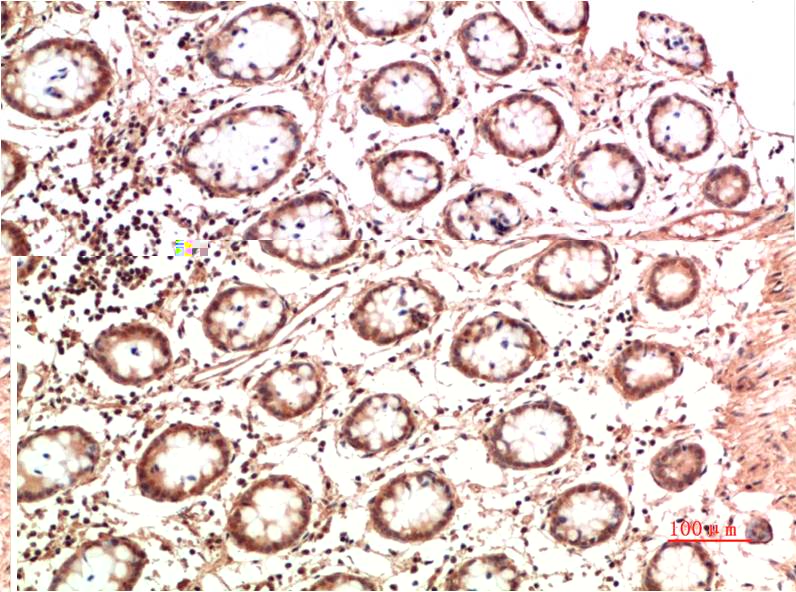

Acetyl P53(K382) Mouse Monoclonal Antibody(5H10)

Applications :IHC

| Recommended dilutions: | IHC: 1:100-200 |

| Specificity: | The Acetyl P53(K382) Mouse Monoclonal Antibody can detects endogenous Acetyl P53(K382) proteins. |